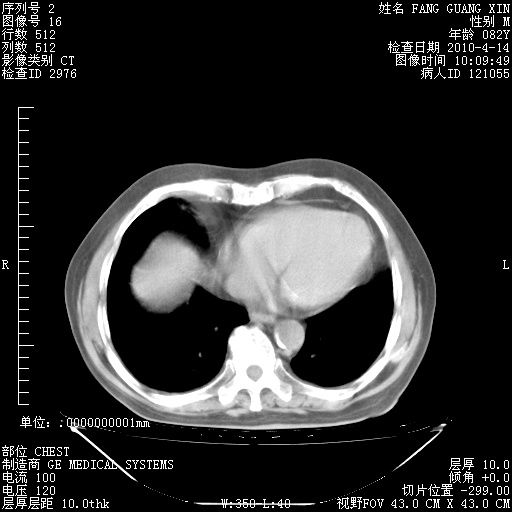

4月14日肺部CT

肺部CT平扫未见异常。